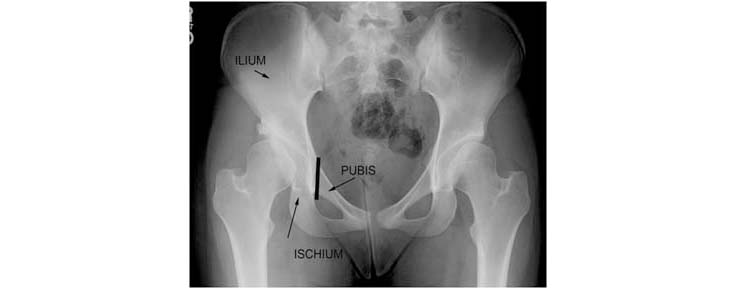

1.This patient's pelvis radiograph (Left) demonstrates hip dysplasia and is compared to a normal pelvis radiograph (Right). The hip dysplasia is more advanced on the right side where the acetabular labrum has been damaged and actually been converted to bone (arrow). The roof of the acetabulum is sloped upward leading to increased pressure within the hip and an increased tendency for the head of the femur to be unstable within the hip joint. This is termed hip subluxation. The presence of increased contact pressures and hip instability leads to hip arthritis in many patients with hip dysplasia.

2.The acetabular index is a measurement of a line formed parallel to the weightbearing zone and the line connecting the base of both hip sockets. In this case it measures 34 degrees. The normal measurement is approximately 6 degrees. A second measurement used in the evaluation of hip dysplasia is called the Center-Edge angle (CE angle). It is measured by drawing a line vertically through the center of the femoral head and a second line from the center of the femoral head to the edge of the hip socket. The angle between these two lines is the Center-Edge angle. In this case, it measures 11 degrees. The normal value for the CE angle is greater than 20 degrees.

Figure 1: Comparative radiographs of the pelvis from a 30 year old female with hip pain and early hip dysplasia (left) and a 49 year old female with underlying hip dysplasia (right) with progression to full-blown advanced hip osteoarthritis. This patient has since undergone hip replacement on both sides.